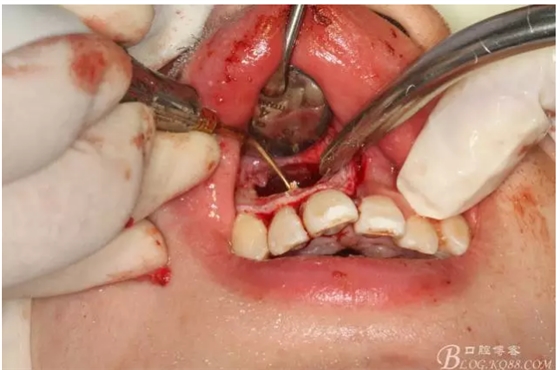

圖2.根管治療術后直接局部 麻醉下切開、翻瓣,發(fā)現(xiàn)12唇側骨壁有綠豆大小骨缺損